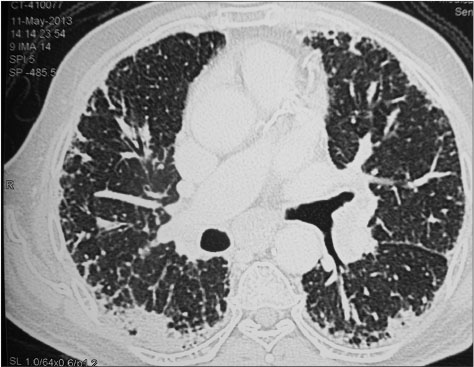

After seven cycles of chemotherapy, the patient presented with weakness, cough, and exertional dyspnea. On examination, the patient was dyspneic on rest and there were bilateral basal crackles in the chest. Initial blood gases were within normal limits. He was started on supportive care with broad-spectrum antibiotics, bronchodilators, and later antifungals. When there was no response to therapy, CT scan of the chest [Figure 4] and [5] and abdomen was done which showed extensive areas of intra- and interlobular septal thickening with fine reticulation in the bilateral lung parenchyma, particularly peripherally and basal. Abdominal films showed further improvement in liver lesions which were only subcentimeter in size. His blood and bronchial cultures were negative for any pathologic organisms. Despite aggressive supportive care, the patient expired after 2 weeks of admission.

| Figure 4 Post treatment computed tomography scan chest, coronal view

| Figure 5 Post treatment computed tomography scan chest, lateral sagittal view